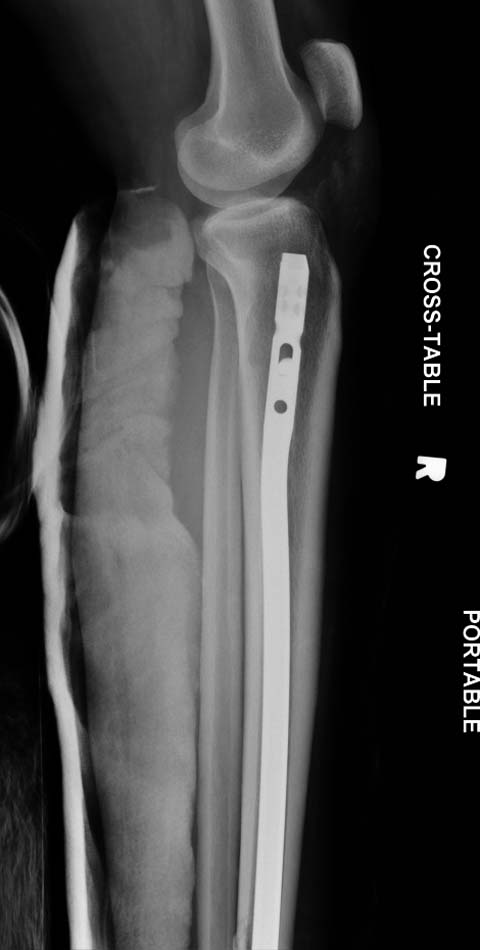

набора гвоздей повлияло на выбор короткого имплантата, имеется угловая и

ротационная деформации. Независимо от локализации, стабильность

создается, когда гвоздь проксимально не глубже 1.5 см (облегчает

удаление) и дистально доходит до epiphyseal scar.

Здесь несколько снимков изолированного перелома большеберцовой с

интактной малоберцовой.  Weber clamp, блокирующие спицы и риминг в

центре канала отрепонировал перелом....